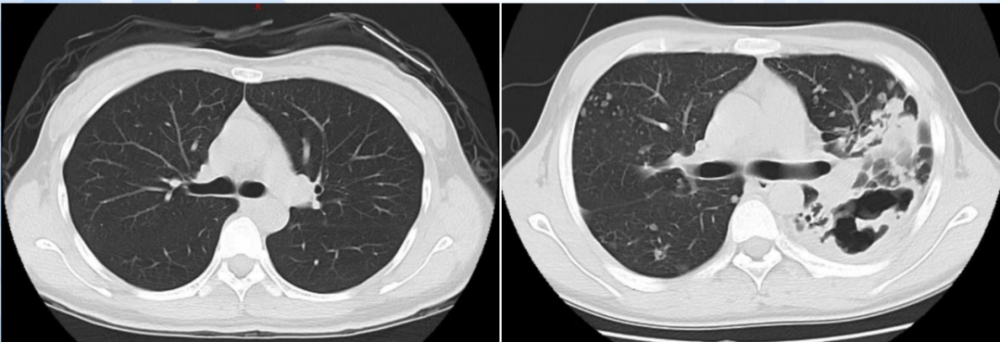

求助可以诊断干酪样肺炎吗

干酪性肺炎——丁香园

图1:患者左主支气管管壁均见大量白色干酪坏死物附着.